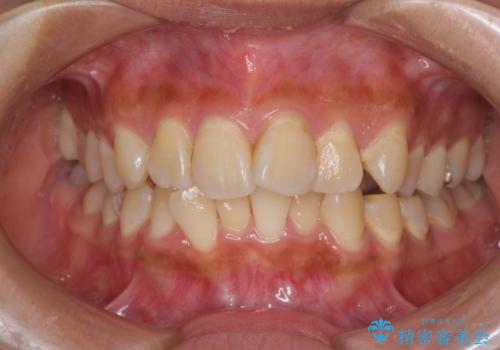

デコボコで磨きにくい前歯をスッキリと インビザライン矯正

- 虫歯が多く、磨きにくい歯並びを改善したいとのことで来院された患者様です。

歯列は叢生が認められる程度でしたが、やや前突感があったので、少しでも口が閉じやすくなるように仕上げる方針としました。

歯磨きしやすくなるとともに、飛び出していた前歯も引っ込めて整えることができました。